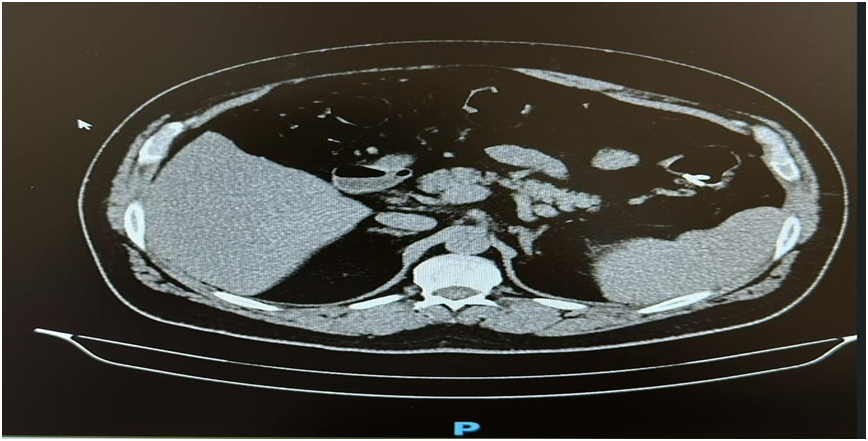

· CT Angiography:

- Dilated colonic veins in the right colon

- No evidence of splenomegaly, portal vein thrombosis, or liver cirrhosis

· Doppler Ultrasound of the Portal Circulation:

- Normal portal vein flow

- No sonographic signs of portal hypertension